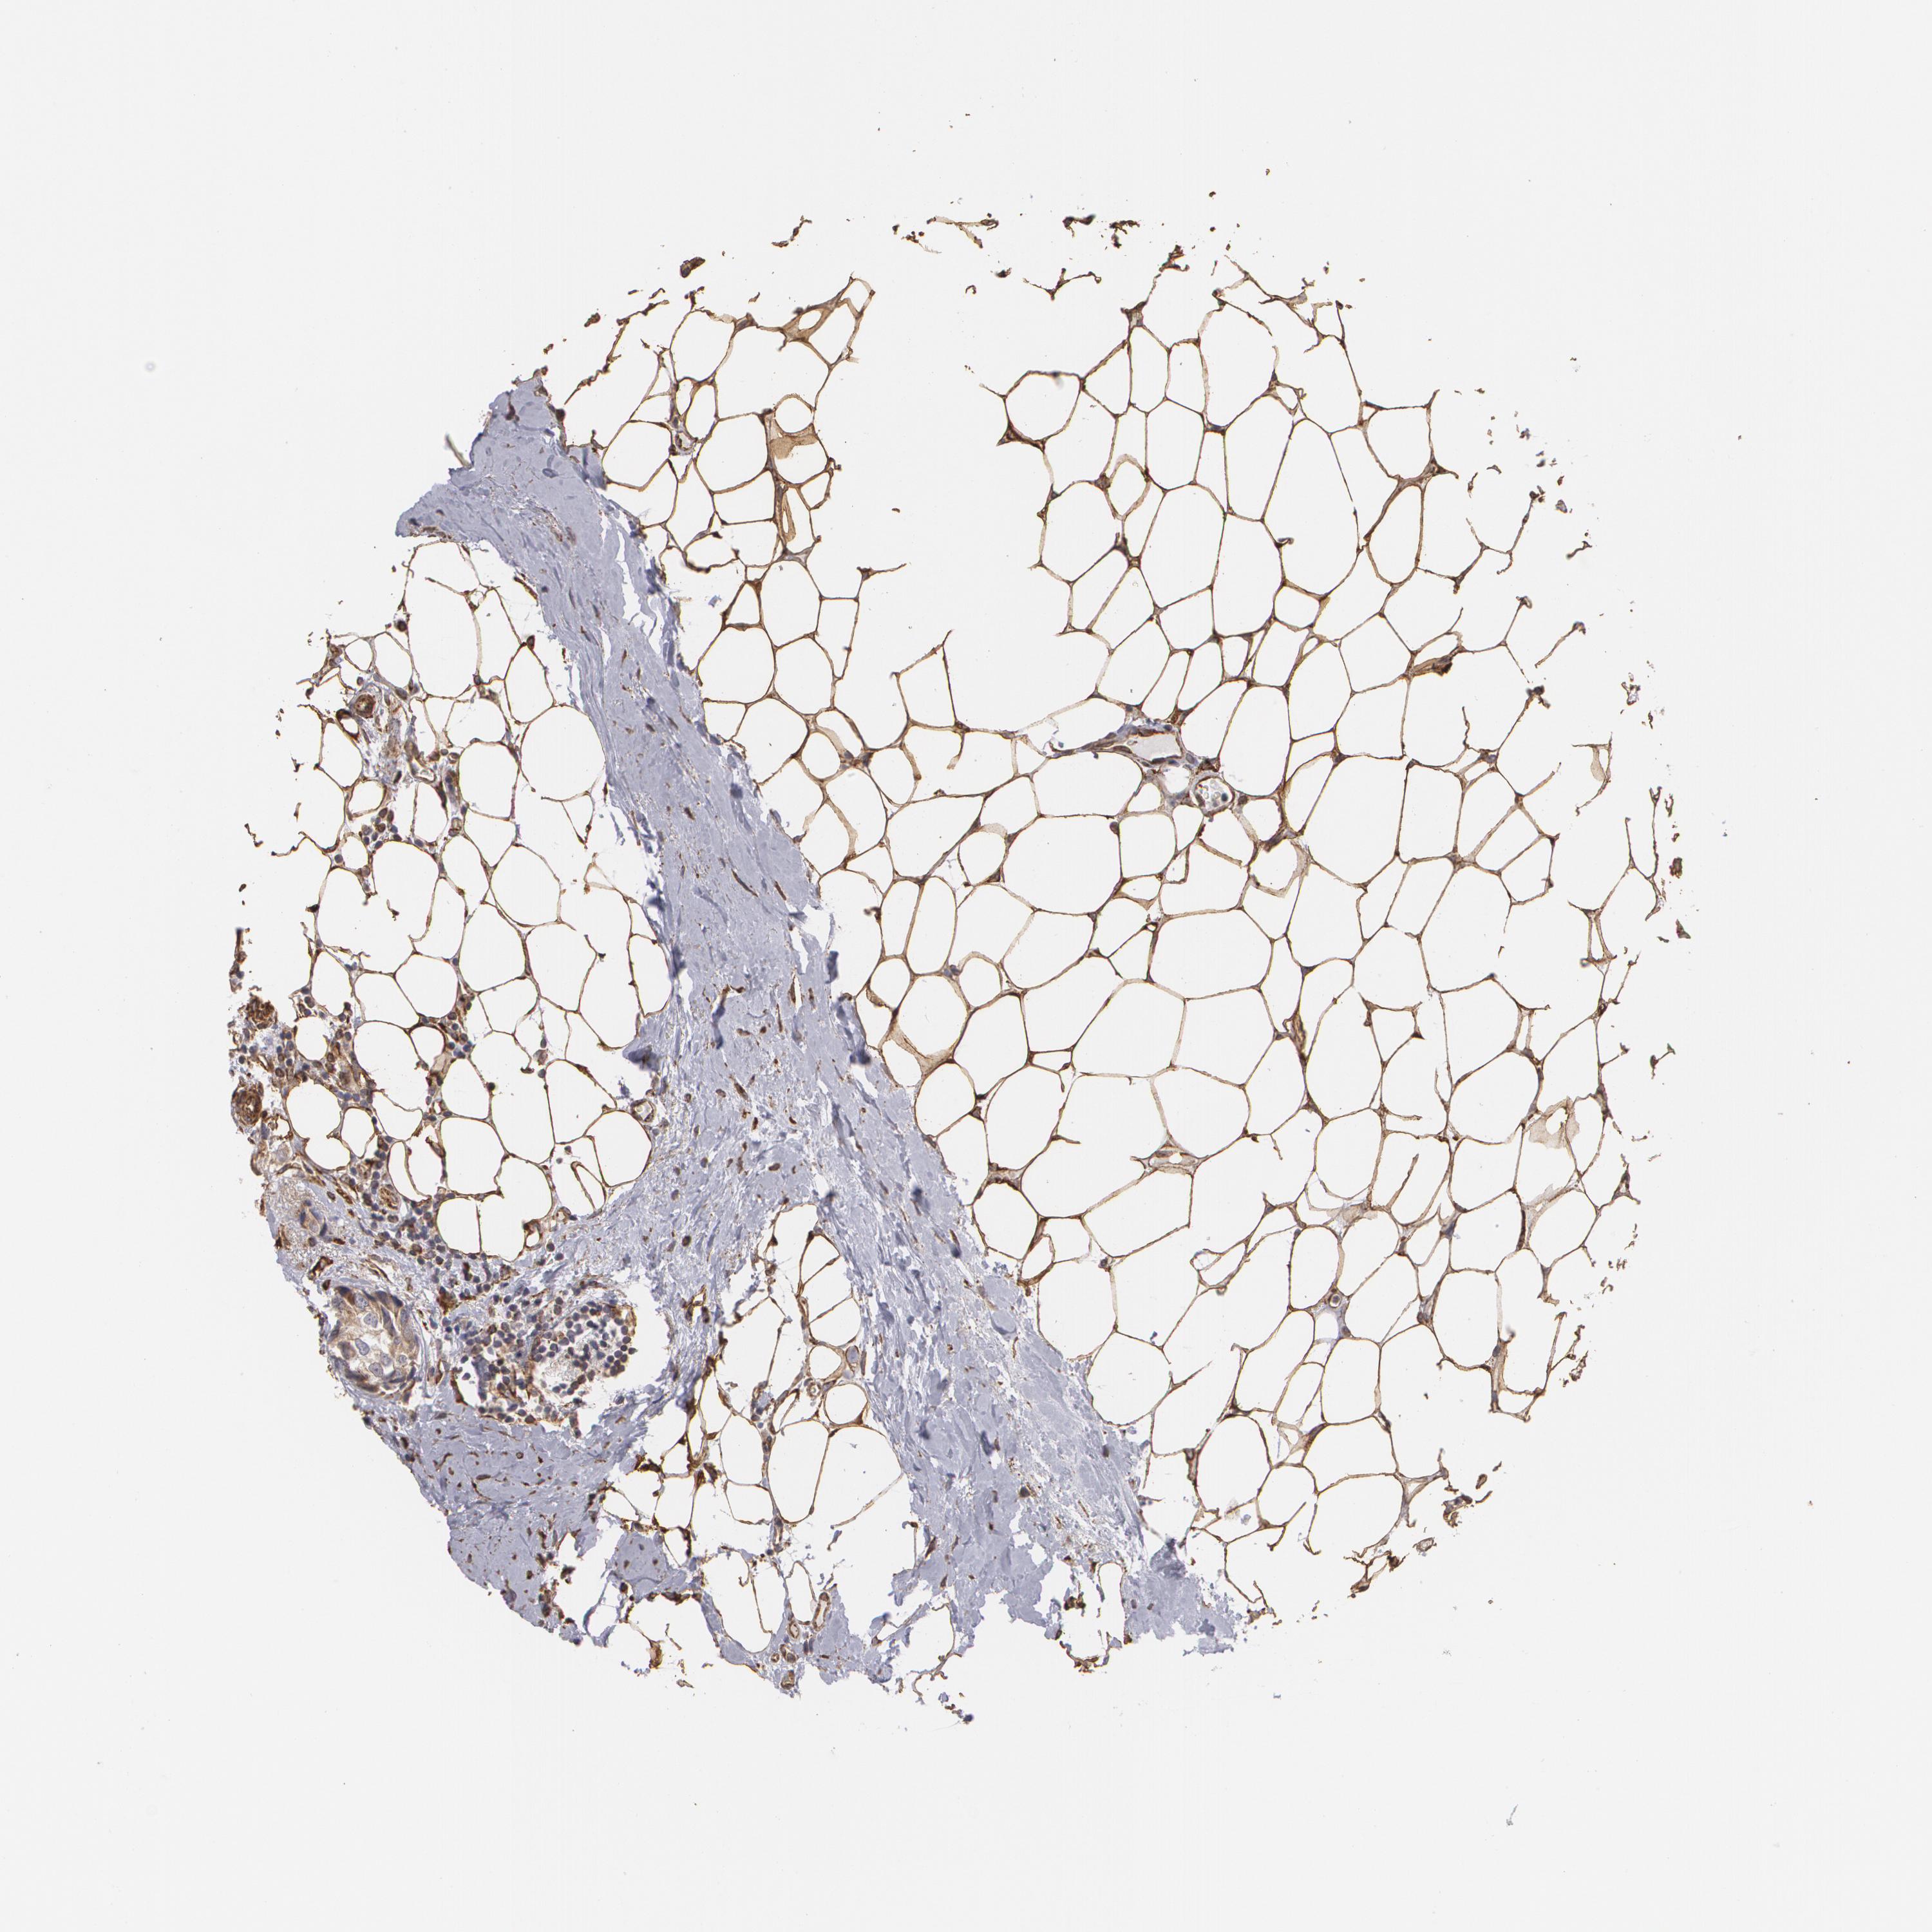

BRCA TCGA BRCA VALIDATION PROTEIN EXPRESSION

ANTIBODIES

AND

VALIDATION